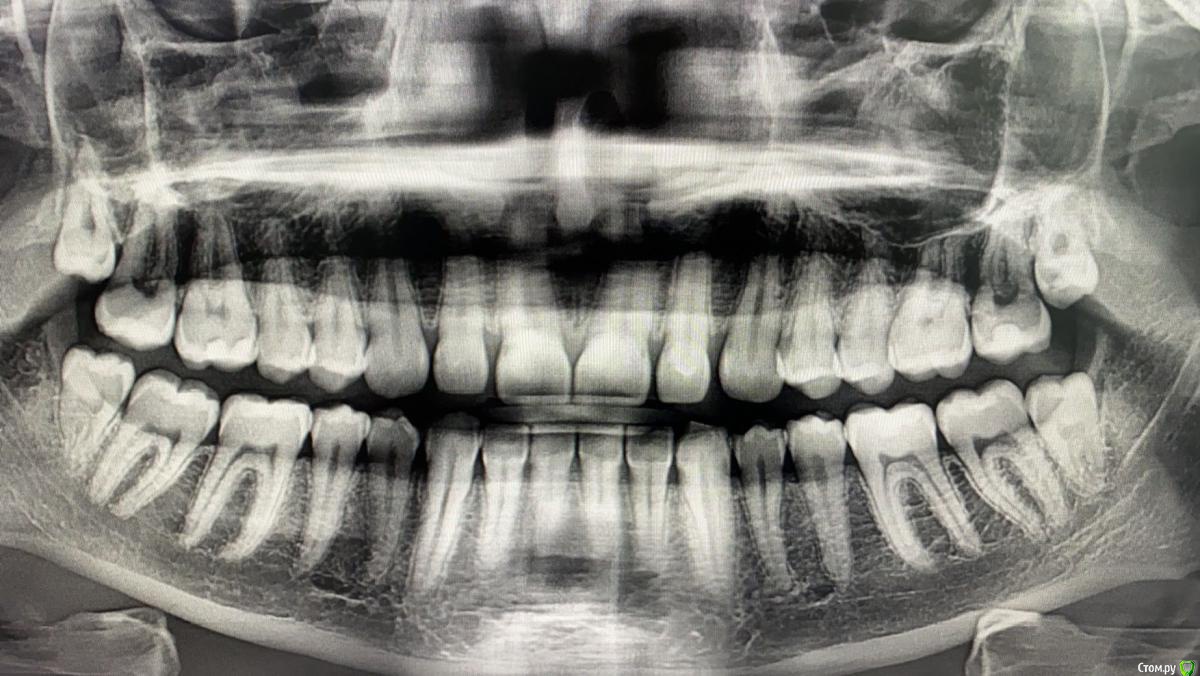

Daria___ Опубликовано 8 декабря, 2019 Поделиться Опубликовано 8 декабря, 2019 (изменено) День добрый. На данный момент нахожусь в другой стране и столкнулась с проблемой зуба мудрости- зуб с левой стороны челюсти не до конца прорезан и находится под капюшоном. Далее всё как по книжке- ноющая боль, небольшое воспаление,потом нагноение под капюшоном. Температуры и отёка пока нет. Сходив к местному врачу получила рекомендацию на удаление зуба. Причем сразу с зубом- антагонистом.Отправила рентген своему семейному врачу: он сказал что места под зуб маловато, но, в целом зуб выглядит пока не плохо. получила рекомендацию полоскать рот мирамистином и раствором соли и ждать как зуб покажет себя в прогрессеЗуб болит уже неделю, полоскания вомпроизвожу 2-3 раза в день третий день. Нагноения вчера после полоскания стало даже немного больше, на что мой отец высказал мнение что это не показатель распространения инфекции, а соль вытягивает гной на поверхность. В общем, у меня тут уже целый консилиум, а что делать так и не решилась. Ибо всё же другая страна, на операцию идти немного боязно ввиду своей правовой незащищенности, хотя многие люди этого врача рекомендовали, в том числе по операции по удалению сложного зуба мудрости. Надеюсь на дополнительные профессиональные отзывы о данной ситуации. Удалять зуб(ы)? Иссекать десну? Продолжать полоскать и ждать? Изменено 8 декабря, 2019 пользователем Daria___ Ссылка на комментарий